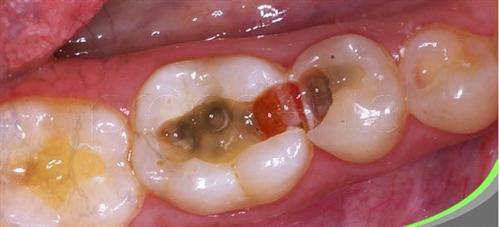

深龋治疗要点是什么 深龋的治疗除了依据龋病的治疗原则之外,必须正确认识深龋对牙髓组织可能产生的影响。深龋对牙本质-牙髓复合体的影响虽然早在釉质龋时,牙髓就开始出现反应,但直到龋损前... 牙齿治疗 阙德厚 553 2024-01-26

深龋的治疗方法 深龋的治疗方法,应有利于增强牙髓的防御能力,消除牙随早期炎症,保护牙髓的功能。在治疗过程中要特别注意避免物理性刺激,如机械损伤、摩擦产热、冷水激,也应避免化学性... 牙齿治疗 速俨 620 2023-12-01

深龋的治疗方法有哪些 去净龋坏组织是龋病治疗原则,但应尽量不穿通牙髓,特别是在急性龋时,牙本质脱矿过程进展快,病变组织中细菌侵入相对较浅,去腐质时不必将所有的软化牙本质去净,但洞侧壁... 牙齿治疗 富南烟 665 2023-11-27